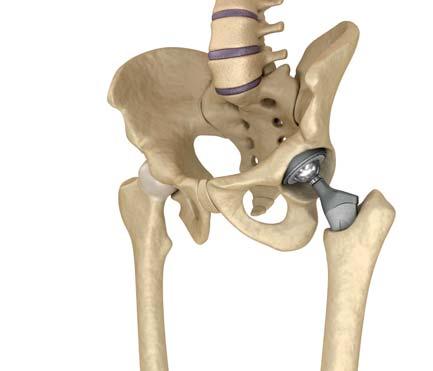

Die Erfolgsquote beim Hüftgelenkersatz ist hoch, Betroffene sind in der Regel sehr zufrieden. Trotzdem darf der Eingriff nicht unterschätzt werden. Wie jede andere Operation birgt auch diese Risiken. Dazu gehören Blutverlust oder die Gefahr von Infektionen. Letztere liegt bei etwa 1%.

Genesung braucht Zeit

Das Gelenk darf und soll zwar bereits kurz nach dem Eingriff belastet werden. Bis sich Operierte wieder vollständig fit fühlen, vergehen im Schnitt allerdings 2 bis 3 Monate. Frühestens nach einem Jahr sind Kraft, Beweglichkeit und Ausdauer so weit hergestellt, wie es mit der Prothese möglich ist. Eine gute Physiotherapie ist dabei ausschlaggebend. Auch bei erfolgreicher OP und Nachbehandlung darf nicht damit gerechnet werden, die ursprüngliche Funktionsfähigkeit wiederzuerlangen.

Entzündung des Hüftgelenks

Die Lebensdauer einer Prothese – die Zeit bis zur Lockerung – liegt heute bei 15 bis 25 Jahren. Danach muss die Prothese ersetzt werden, um der Schädigung von Knochenmaterial vorzubeugen. In etwa 10% der Fälle ist eine Wechseloperation bereits früher nötig.

■ Grundsätzlich gilt: Geht es um das Einsetzen einer Hüftprothese, kann man kaum zu spät operieren. Ist der Leidensdruck gross, drohen chronische Fehlhaltungen, sind die konservativen Behandlungsmethoden ausgeschöpft und einer Gelenkersatzoperation steht nichts im Wege, kann eine Prothese die Lebensqualität Betroffener stark erhöhen.